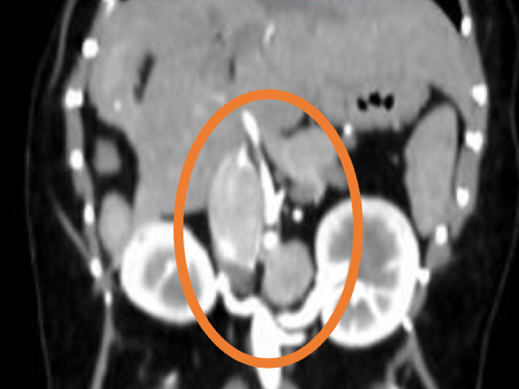

膀胱結石の精査目的で他院にてCT検査を実施したところ、左副腎に腫瘍性病変が認められ、後大静脈への浸潤も確認されました。 これを受けて、手術目的で当院を受診されました。 当院にて褐色細胞腫摘出術を実施し、術後は体調良好であったため、術後4日目に退院されました。

手術前のCT検査にて腫瘍の浸潤・転移チェックを実施